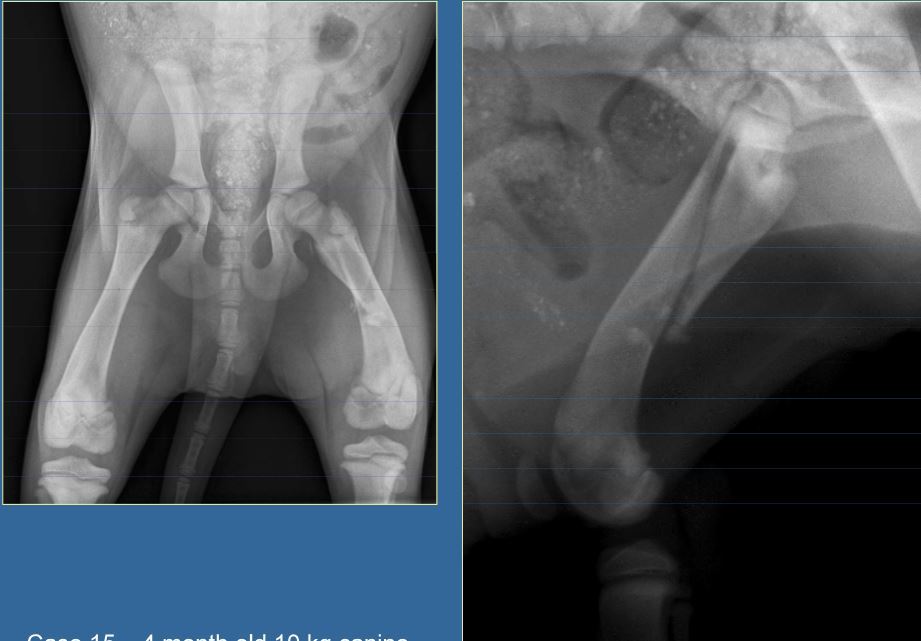

4 month old canine, 10kg

HBC 24 hours ago

Classify and assess fracture, and give repair options

A

Long oblique fracture of the proximal femoral diaphysis

Fx score= 8-10

Repair: IM pin+ cerclage wire, ESF, bone plate